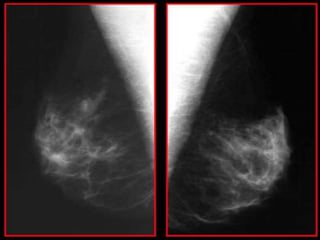

Durante os exames radiográficos das mamas, realiza-se as

incidências mamográficas mais comuns crânio caudal

(CC) e médio lateral oblíqua (MLO).

Durante os examesradiográficos das mamas, realiza-se as incidências mamográficas mais comuns crânio caudal (CC) e médio lateral oblíqua (MLO).